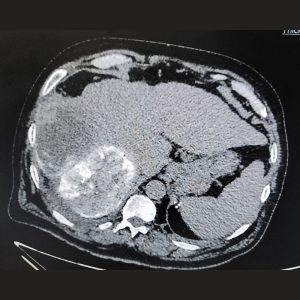

3. Tumor Ablation (Radiofrequency/Microwave)

The Problem: Small to medium-sized tumors in the liver, kidney, lung, or bone that need to be destroyed.

Our Solution: Under precise CT or Ultrasound guidance, a thin probe is inserted directly into the tumor. The tip then emits either radiofrequency (heat) or microwave energy, completely destroying the cancerous cells in a controlled zone.

Patient Benefit: A true scarless “surgery” that eradicates tumors without an incision. It preserves maximum healthy organ function and is often a curative option for early-stage cancers.